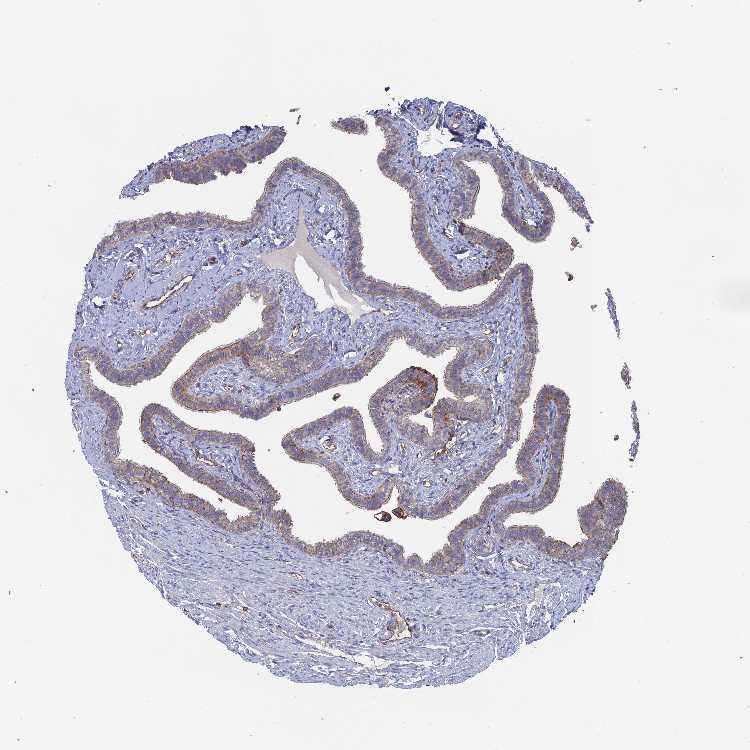

SNX11